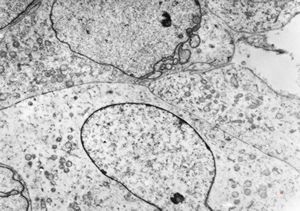

F,32y. | transversally sectioned skeletal muscle cell

mouse skeletal muscle cell - transversal section